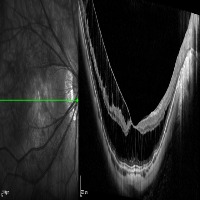

Medical Imaging Analysis: The "three-segment" model can be used by healthcare professionals for enhanced analysis of medical imaging, such as MRI or CT scans. It will help in identifying cleave classes, which can improve detection and diagnosis of potential issues in the brain, particularly those related to retina or neural connections.

Retinal Disease Diagnosis: Ophthalmologists could utilize the model to get help in diagnosing retinal diseases. It can help to identify any abnormalities by differentiating between the 'out', 'in', and 'retina' segments, enabling early detection of conditions such as retinal detachments or macular degeneration.

AI in Surgery: The model can be used to assist surgeons during complex neuro or eye surgeries. It can provide enhanced visualization, enabling real-time differentiation between various segments, leading to more precision in surgical procedures.

Medical Training and Education: The model can be used in medical learning settings, providing students with valuable visual learning material. It could serve as an advanced tool for the understanding of the retina and other segments of the brain or eye.